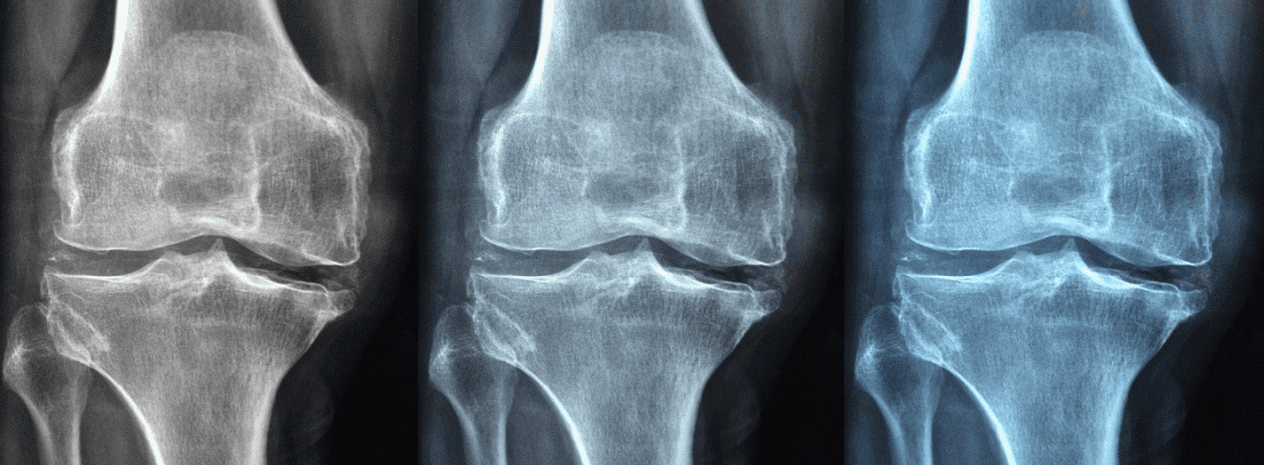

골밀도가 정상치보다 낮은 경우 골다공증이라고 말하며, 넘어짐 등의 충격에 뼈가 쉽게 골절되는 현상이 발생합니다. 그래서 뼈의 밀도를 높이는 것이 중요한데, 칼슘이 대표적인 뼈를 강하게 하는 영양소로 우유, 치즈, 요구르트, 브로콜리, 케일, 아몬드 등의 음식이 칼슘이 많이 포함되어 있습니다.